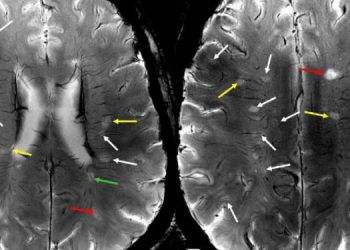

ЧИТАТЬ ВСЕХотя роль сосудистой патологии при поражениях рассеянного склероза (РС) была предложена давно, выведение этих поражений из сосудистой системы было трудно...